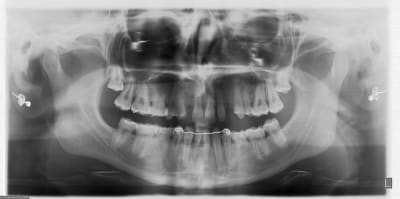

jeune homme,

18 ans,

agénésie de 12,

extraction de 52 depuis 2 ans et remplacement par un mainteneur d'espace, vient consulter pour un implant...

j'adore ce genre de cas, c'est un vrai défi esthétique où on a pas le droit à l'erreur.

je pense qu'une greffe osseuse serait peut être nécessaire pour la concavité. Toutefois, je devrais pouvoir m'en sortir en dilatant la crête osseuse vestibulaire pendant la pose de l'implant.